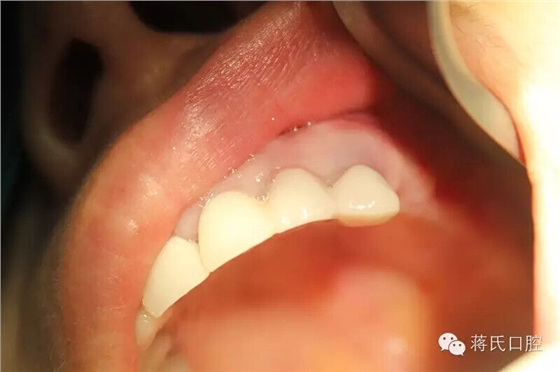

18.修復(fù)完成后口內(nèi)